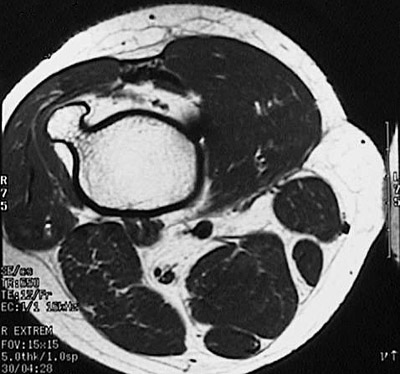

This axial MRI scan demonstrates an osteochondroma projecting laterally from the metaphyseal region of the distal femur.